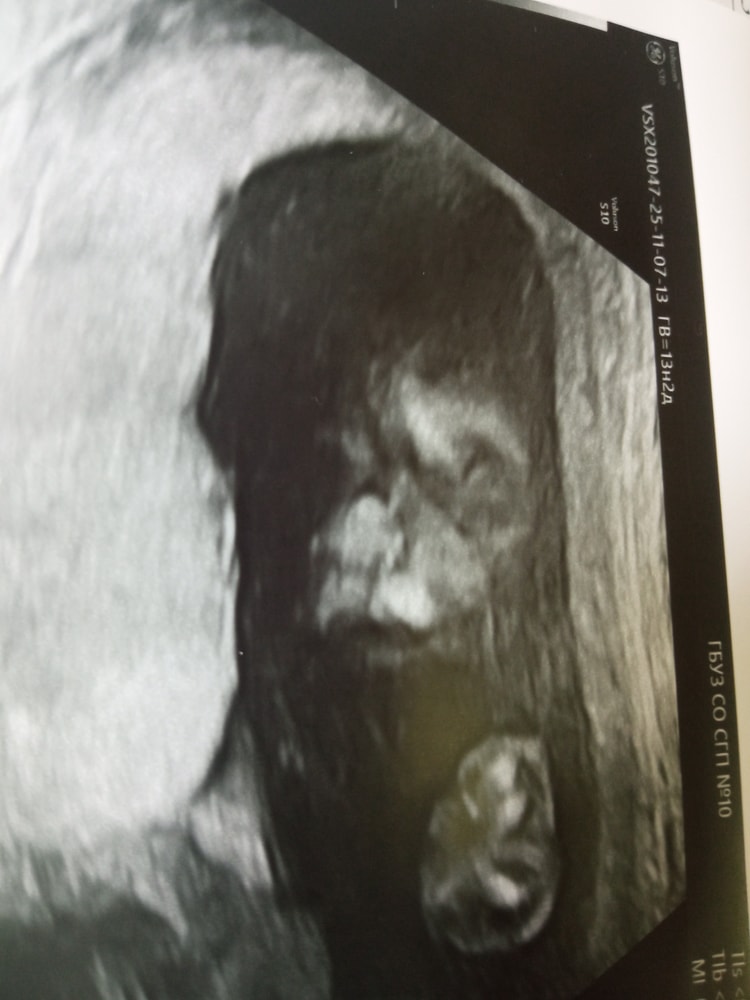

УЗИ на 20 недели

Не помню уже на каком сроке, но +- около 20 недель исключили данную патологию (был впр при котором возможны сопутствующие пороки тоже, поэтому исключала по мере роста малышки). Узи всю беременность делала у Киселева в медгарде где клиники университета. По факту что было по узи, так и родилась, очень хорошо смотрит

У нас более четко было ее видно. Сперва предполагали двустороннюю, но на экспертном узи, поставили одностороннюю.

По снимку на узи будто есть, но важнее что говорит доктор. Можно сделать и в др клинике узи. Плюс это спокойно корректируется после рождения 🙏🙏🙏

А что вам узист сказал ? Если сомневаетесь сделайте 3 д узи

25 недель. Фуфломицины, УЗИ и старые тревоги 1 скрининг (второе мнение)